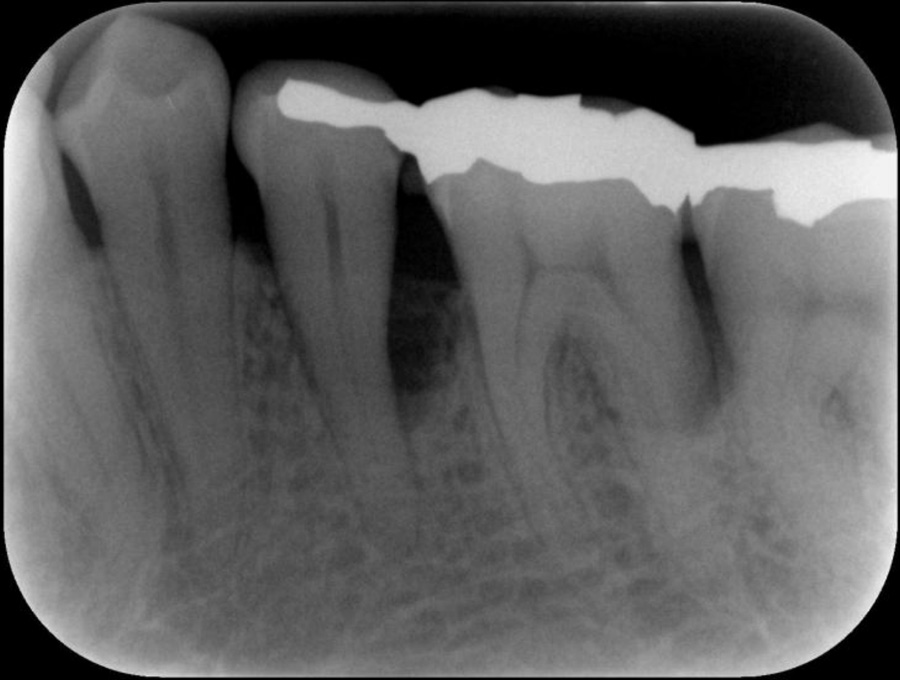

正確な診断

歯周ポケット測定やレントゲン・CT解析など、多角的な検査で歯周病の進行度と原因を正確に把握します。患者さま一人ひとりに最適な治療計画を立て、根拠ある治療につなげます。

精密検査

実際にお口の中の状態をチェックしていきます。レントゲン撮影にて歯や骨の検査を行い、虫歯や治療痕のチェック、歯周病検査などの各種検査を行い、総合的な診断を下します。